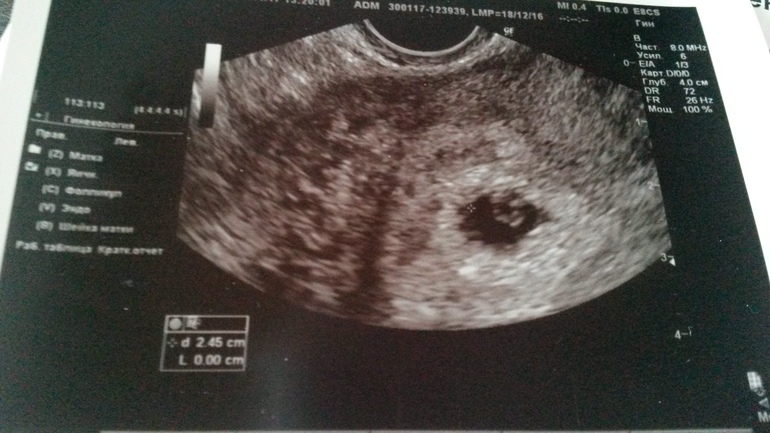

6 недель

Сегодняшние новости. Такой малыш, а сердечко уже бьется. Так волнуюсь за этого кроху. В первую беременность вообще не думала и не берегла себя, а сейчас прислушиваюсь к каждому шороху в животе. Трепет в душе... Думаю, что мальчик, без вариантов. Я и в первый раз с самого начала знала, так же и сейчас знаю.

Поздравляю!)подскажите,а вы были на консультации врача с результатами узи?я сегодня на узи была,срок 6 недель,частота сердцебиения 100 (у вас смотрю 98),мне врач сказала это мало( переживаю очень

Надежда

Сегодня была у врача. Ее тоже смутила редкость сердцебиения, и она меня направила сразу же сделать еще одно узи. На этот раз поставили 109 ударов в минуту, но это среднее. То есть там доходило и до 130 даже, но среднее 109. Мне сказали, что все нормально, волноваться не стоит за это.